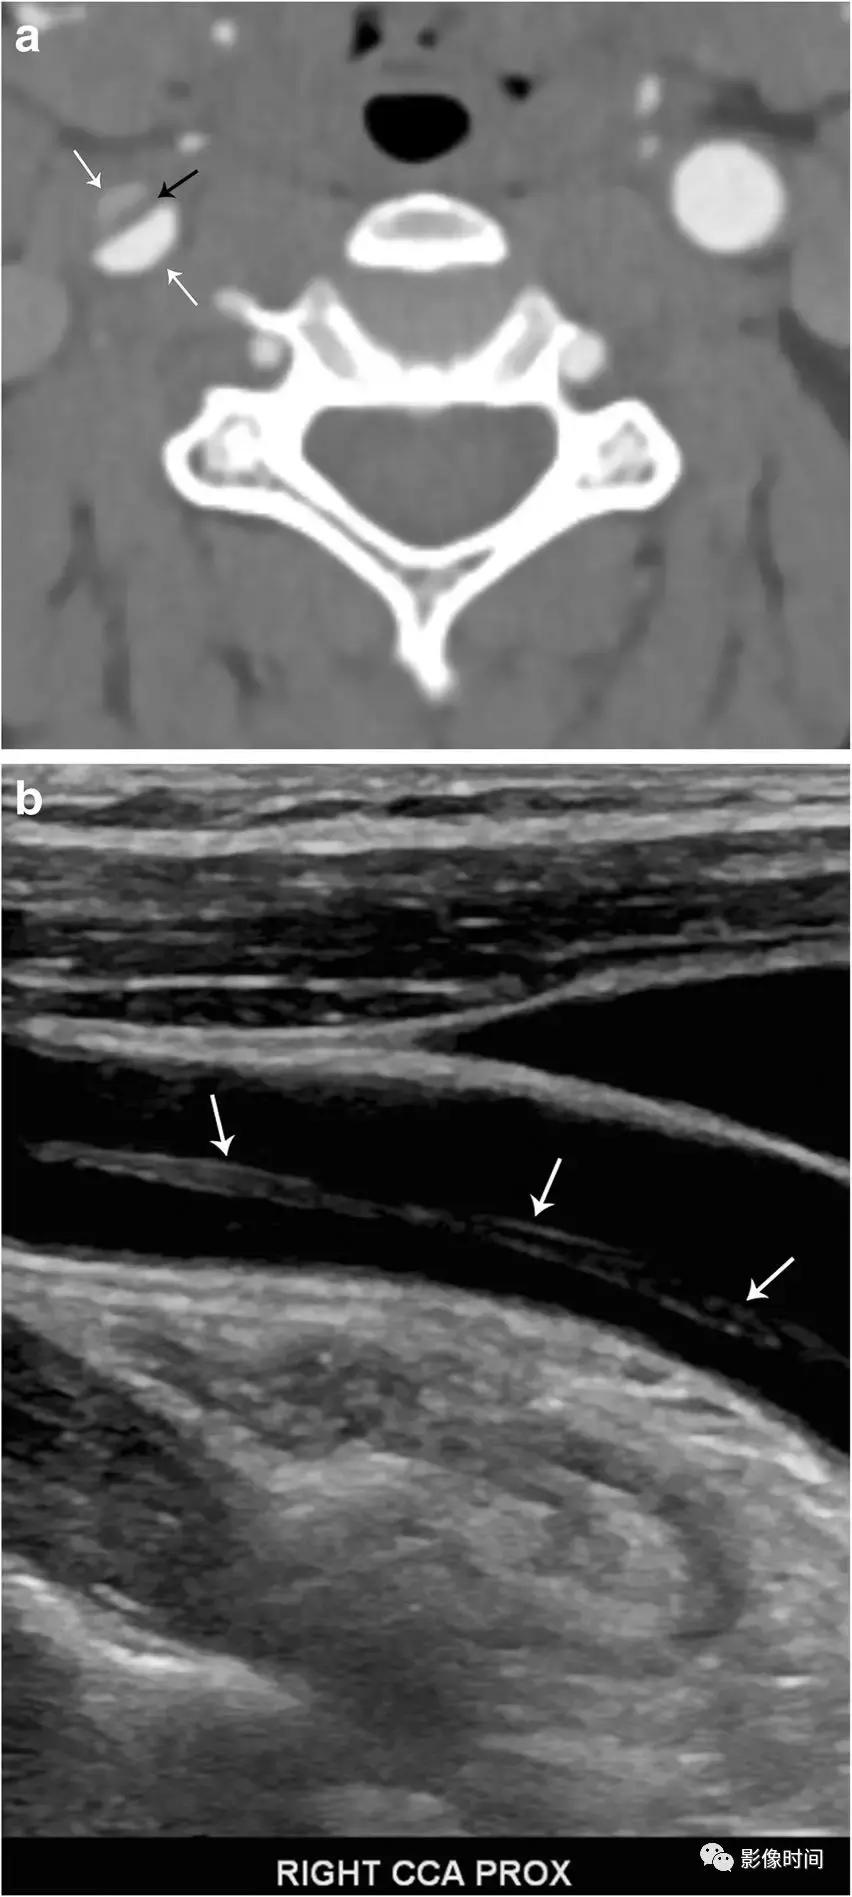

4、颈内动脉/颈总动脉夹层:颈动脉内膜撕裂,血液进入中膜并形成血肿。内膜撕裂可以自发,也可能与外伤或医源性有关。不管是什么原因,通常会导致真正血管腔的狭窄。颈动脉夹层约占 45 岁以下患者脑卒中原因的 20%。典型症状包括疼痛、同侧霍纳综合征和脑缺血症状。DSA 被认为是诊断的金标准,但是侵入性的,只评估管腔直径,而不是观察动脉壁厚度或形态。CTA 提供了更高的空间分辨率来评估管腔和管壁。T1WI 脂肪抑制序列对壁间血肿高度敏感。

模式图显示了颈内动脉夹层,内膜撕裂,血肿位于中膜,真腔狭窄。DSA 显示真腔狭窄 (黑色箭头)。轴位 CTA、超声下显示右颈总动脉有内膜瓣 (黑色箭头) 和「双腔」征 (白色箭头)。轴位 T1WI-压脂显示右侧颈内动脉高信号新月形壁间血肿,真腔明显狭窄,右侧颈内动脉显示正常流空信号。